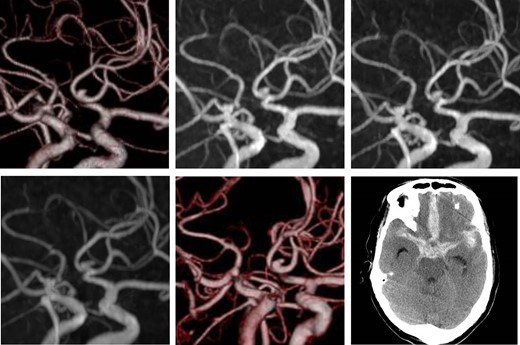

A 73-year-old man was diagnosed with a UIA of the anterior communicating artery (A-com), and had been followed up for 2 years at the outpatient department of the Institution. Computed tomography angiography (CTA) revealed an A-com UIA with a height of 2.7 mm and width of 2.1 mm (Fig. 1, upper-left). During the follow-up using magnetic resonance angiography (MRA), the UIA was considered to be stable (Fig. 1, upper-middle and right). Two years after the initial diagnosis, MRA demonstrated an irregular shape of the aneurysm (Fig. 1, lower-left), and further CTA examination revealed a newly emerged bleb on its surface (Fig. 1, lower-middle).

Initial computed tomography angiogram of the unruptured cerebral aneurysm. A saccular aneurysm, 2.7 × 2.1 mm2 in size, is arising from the anterior communicating artery (upper-left). Follow-up magnetic resonance angiography. Images at 6 months (upper-middle) and 1 year (upper-right) after the initial diagnosis show the unchanged aneurysm. Two years after diagnosis, the shape of the aneurysm changed (lower-left). Computed tomography angiogram shows a de novo bleb (lower-middle). Computed tomography after the aneurysm rupture indicates aSAH (lower-right).

We considered the emergence of the bleb as a risk for early rupture, and planned the surgery. However, 2 weeks after the examination, while the patient was waiting for admission, he developed a sudden headache and was transported to our hospital. Computed tomograms taken on admission showed subarachnoid hemorrhage (Fig. 1, lower-right), and surgery was performed the same day. Surgical findings showed that the bleb was the rupture point. Postsurgical recovery was uneventful, but higher brain dysfunction remained.